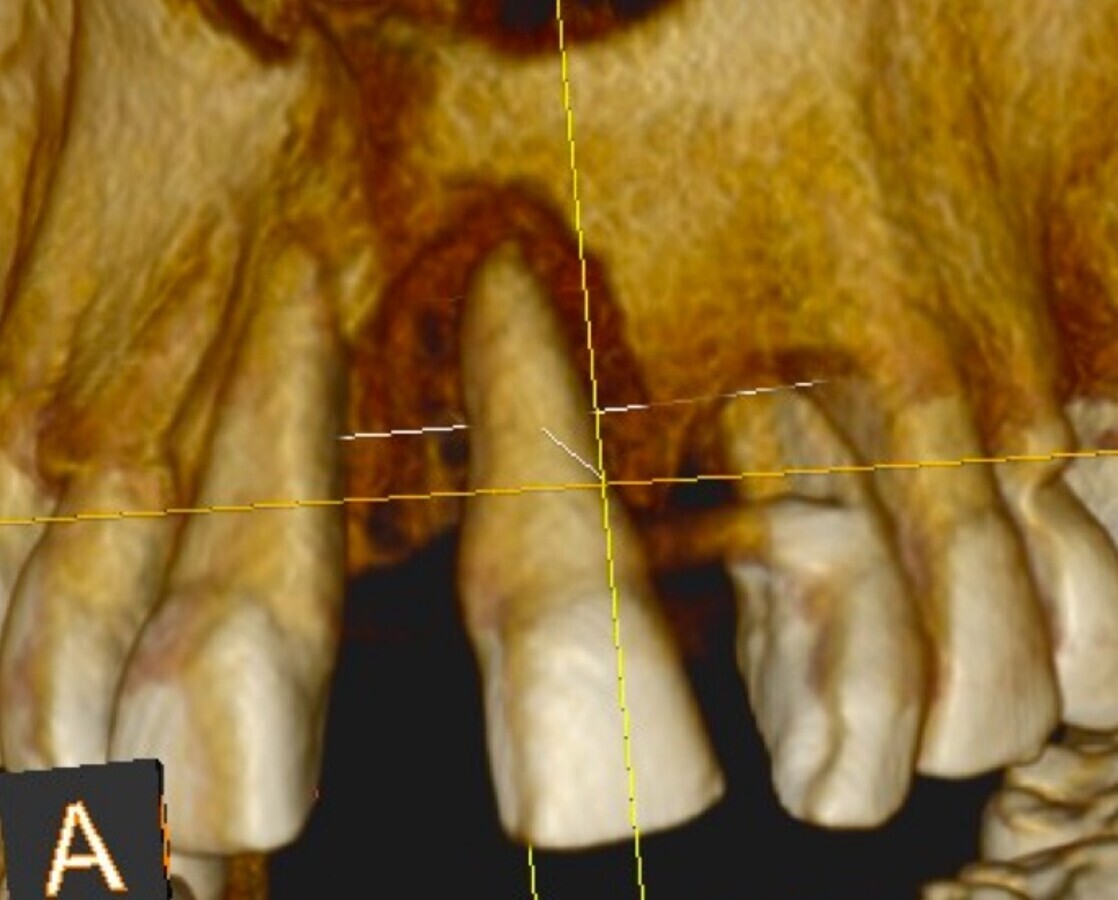

Imagen 8. Cortes tomográficos a nivel de las piezas 12 - 11 y 21 - 22.

En las imágenes se observa el volumen, la regeneración y mantenimiento de las tablas vestibulares de todas las piezas intervenidas, responsables del aspecto de la guirnalda gingival. Sin reabsorción ósea, resultando un tratamiento biológico. “En todo el tratamiento no existe ninguna maniobra clínica, ni del sistema que genere una reacción de defensa que se manifieste como reabsorción, consiguiendo así una integración implanto quirúrgico protético ideal.

Estas situaciones, documentadas desde hace más de 12 años, proporcionan cuadros clínicos más biológicos, estéticos y estables en salud a largo plazo, que se corroboran en las tomografías Cone Bean.

Entendemos conceptualmente como “más biológico” el análisis de las radiografías, tomografías y la estética clínica estable, mostrándonos que el organismo no reacciona a ninguna maniobra a lo largo de todo el procedimiento, hasta la elaboración de la restauración final y se mantiene estable en el tiempo.